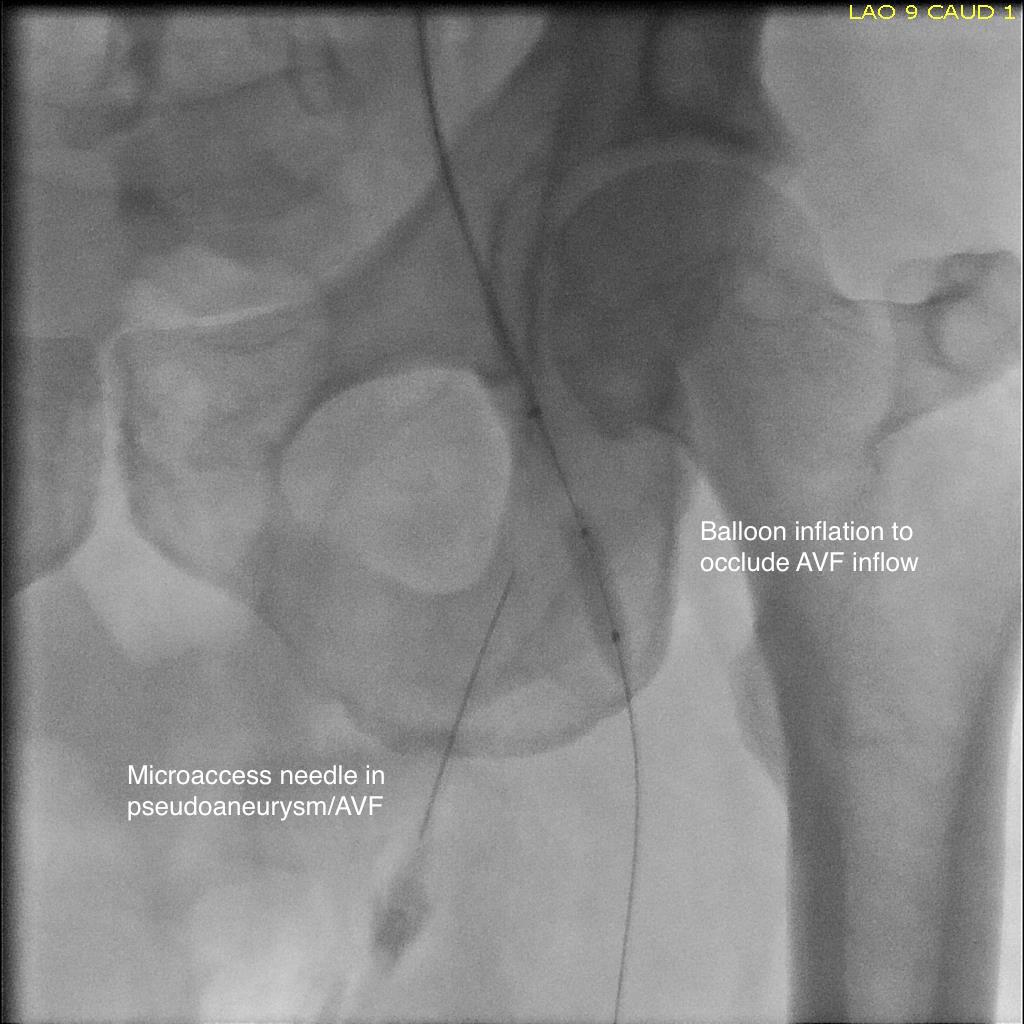

Axial MPR

Operation was planned, but in the days leading up to the operation, I had a thought -the primary reason why ultrasound guided thrombin injection would fail is the AVF. It would be simple to fluoroscopically guide an angioplasty balloon on the arterial side to occlude the fistula inflow. The next step would be to get access to the pseudoaneurysm with a needle under ultrasound guidance, confirm location with a contrast injection. Once confirmed, the balloon is inflated and a small volume of thrombin would be injected. I discussed this with the patient in detail and he was enthusiastic about trying this before proceeding with an open repair.

pseudoaneurysm avf procedure sketch

Schematic of procedure

The procedure went as planned. Ultrasound guided access is aided with dual live display of B-mode and color flow (below)

Arteriography showed much of the contrast from injection of the pseudoaneurysm to preferentially go to the artery which made me worry less about creating a DVT/PE. With balloon inflated (below), thrombin was injected and balloon inflation held for about 30 seconds.

angio procedure31

There was resolution of flow in the pseudoaneurysm and in the fistula. Before and after duplexes are composited below.